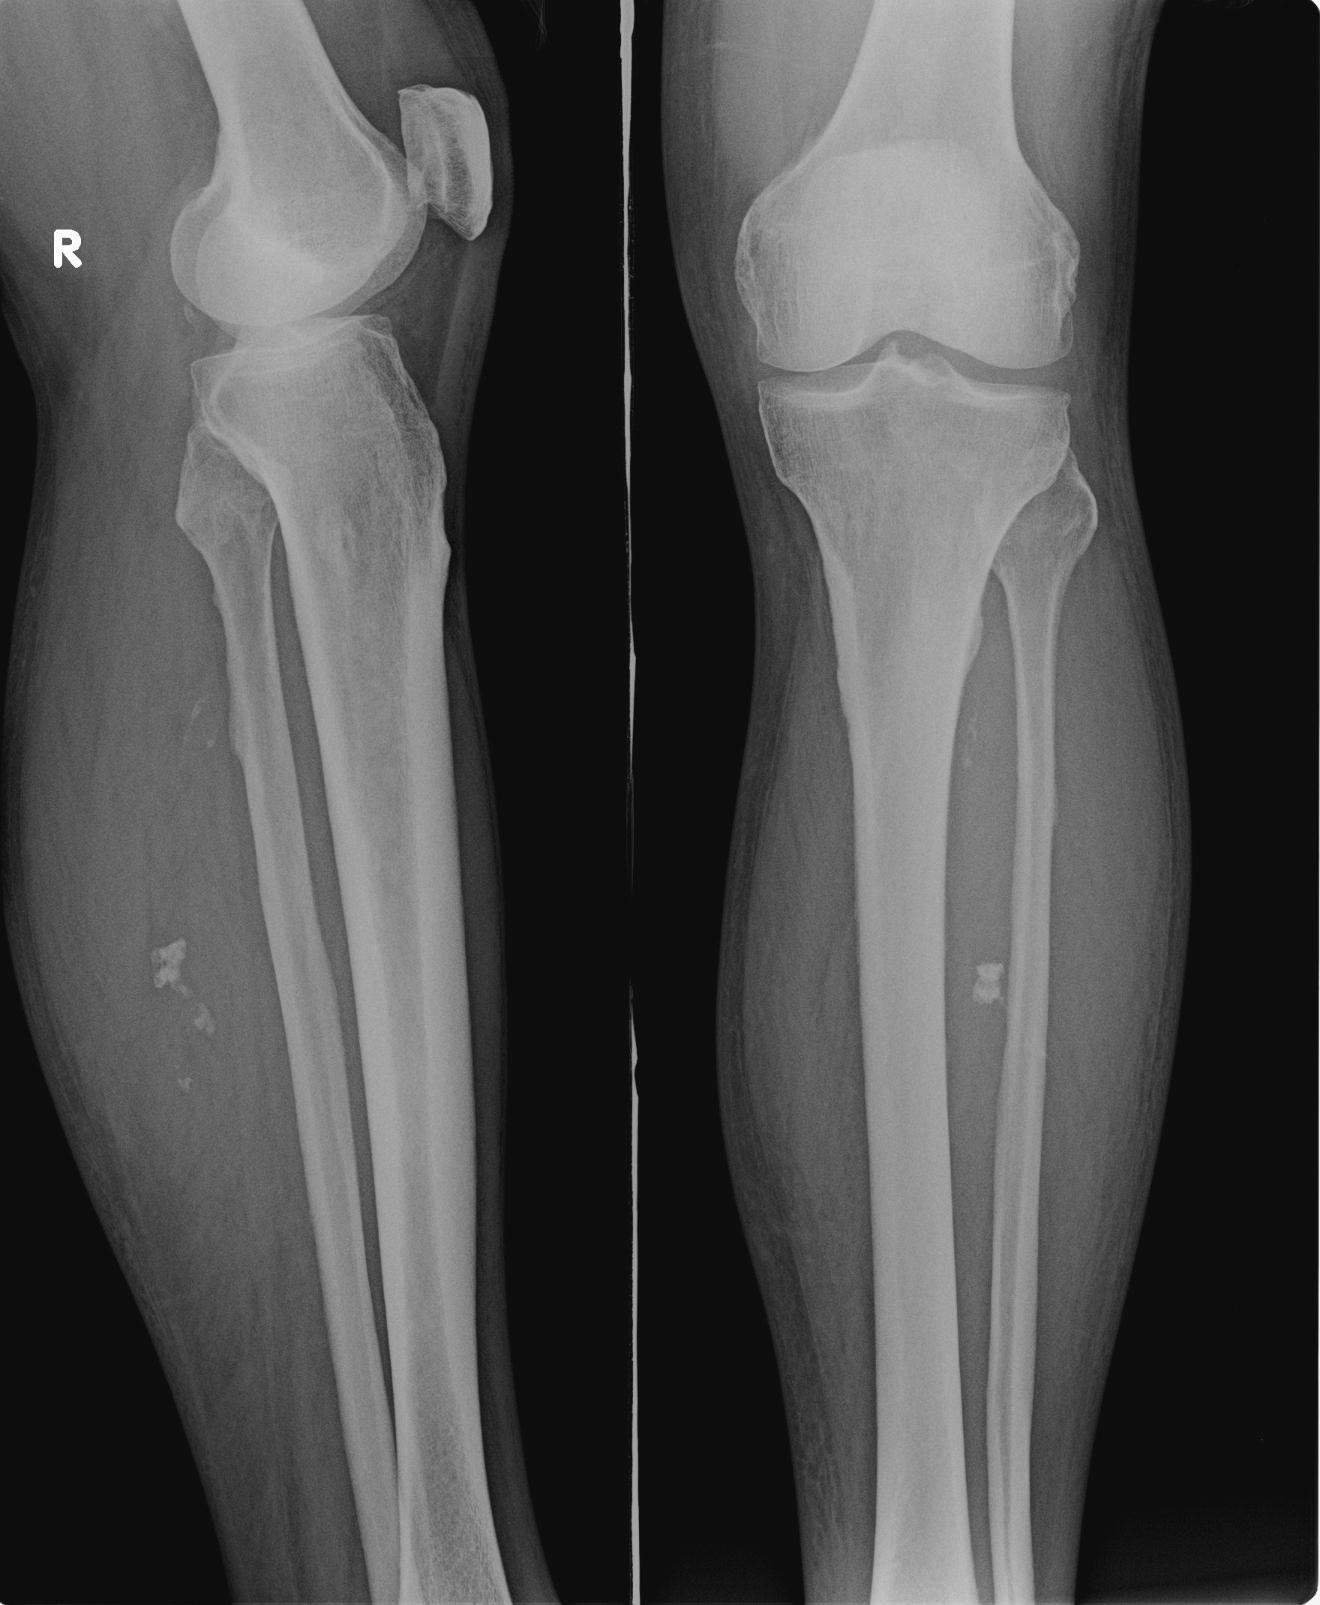

标题: X0965:胫腓骨片,

男 70y,腿部不适,前来就诊

考虑小腿软组织血管瘤或avm伴胫腓骨中上段局限性骨皮质增生,右膝关节退变。

1、右小腿软组织海绵状血管瘤。

2、右膝关节轻度退行性变。

1、软组织内钙化,多考虑血管源性,血管瘤或avm;2、右膝关节退变.